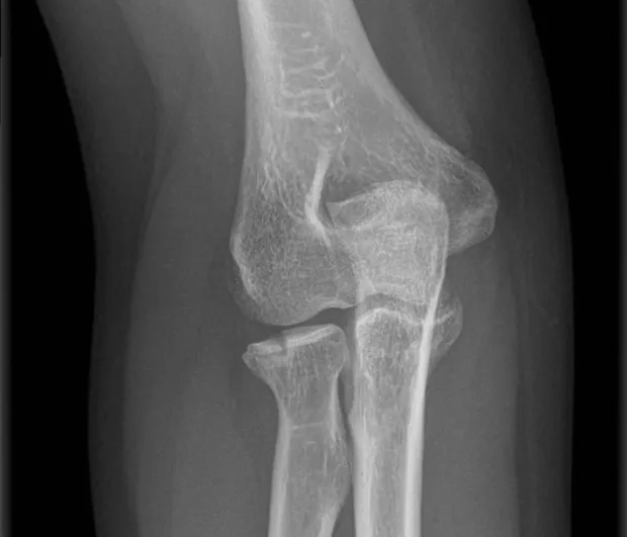

segun clasificacion de Masson que tipo es

Tipo 1 no desplazada

Se busca consolidación primaria para que no haya callo visible ya que es una articulacion y no queremos ese callo ahí